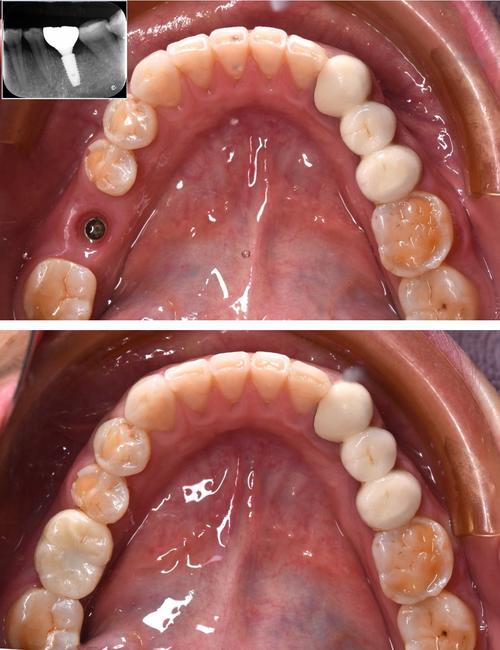

美国植体适用范围广泛,涵盖各类缺牙情况,单颗牙缺失患者可通过种植体恢复独立牙根,避免邻牙磨损;多颗牙缺失者可种植桥或覆盖义齿,无需摘戴;全口无牙患者可选择All-on-4/6技术,仅需4-6颗植体支撑半口牙列,大幅降低创伤,对于骨量不足的患者,配合植骨、骨增量技术或短植体(长度≤8mm)也能实现成功种植,对咀嚼功能、美观效果要求较高的患者,以及有系统性疾病(如糖尿病、骨质疏松)但病情稳定的群体,在医生评估后也可安全使用。

选择美国植体时,需综合考量多方面因素,品牌方面,Nobel Biocare(诺贝尔)、Straumann(士卓曼)、Zimmer(捷迈)等一线品牌临床数据更完善,长期成功率超95%,但价格相对较高;中端品牌如BioHorizons(碧兰)性价比突出,适合预算有限者,医生技术与经验至关重要,建议选择具备口腔种植专科资质、案例丰富的医生,其能根据患者骨条件、咬合习惯制定个性化方案,医院设备需配备CBCT、数字化口扫、无菌手术室等,为精准手术提供保障,自身条件方面,需确保口腔无未控制的炎症(如牙周炎),全身健康状况稳定(如血压、血糖达标),质保年限也是参考指标,正规品牌通常提供10-20年的质保服务。